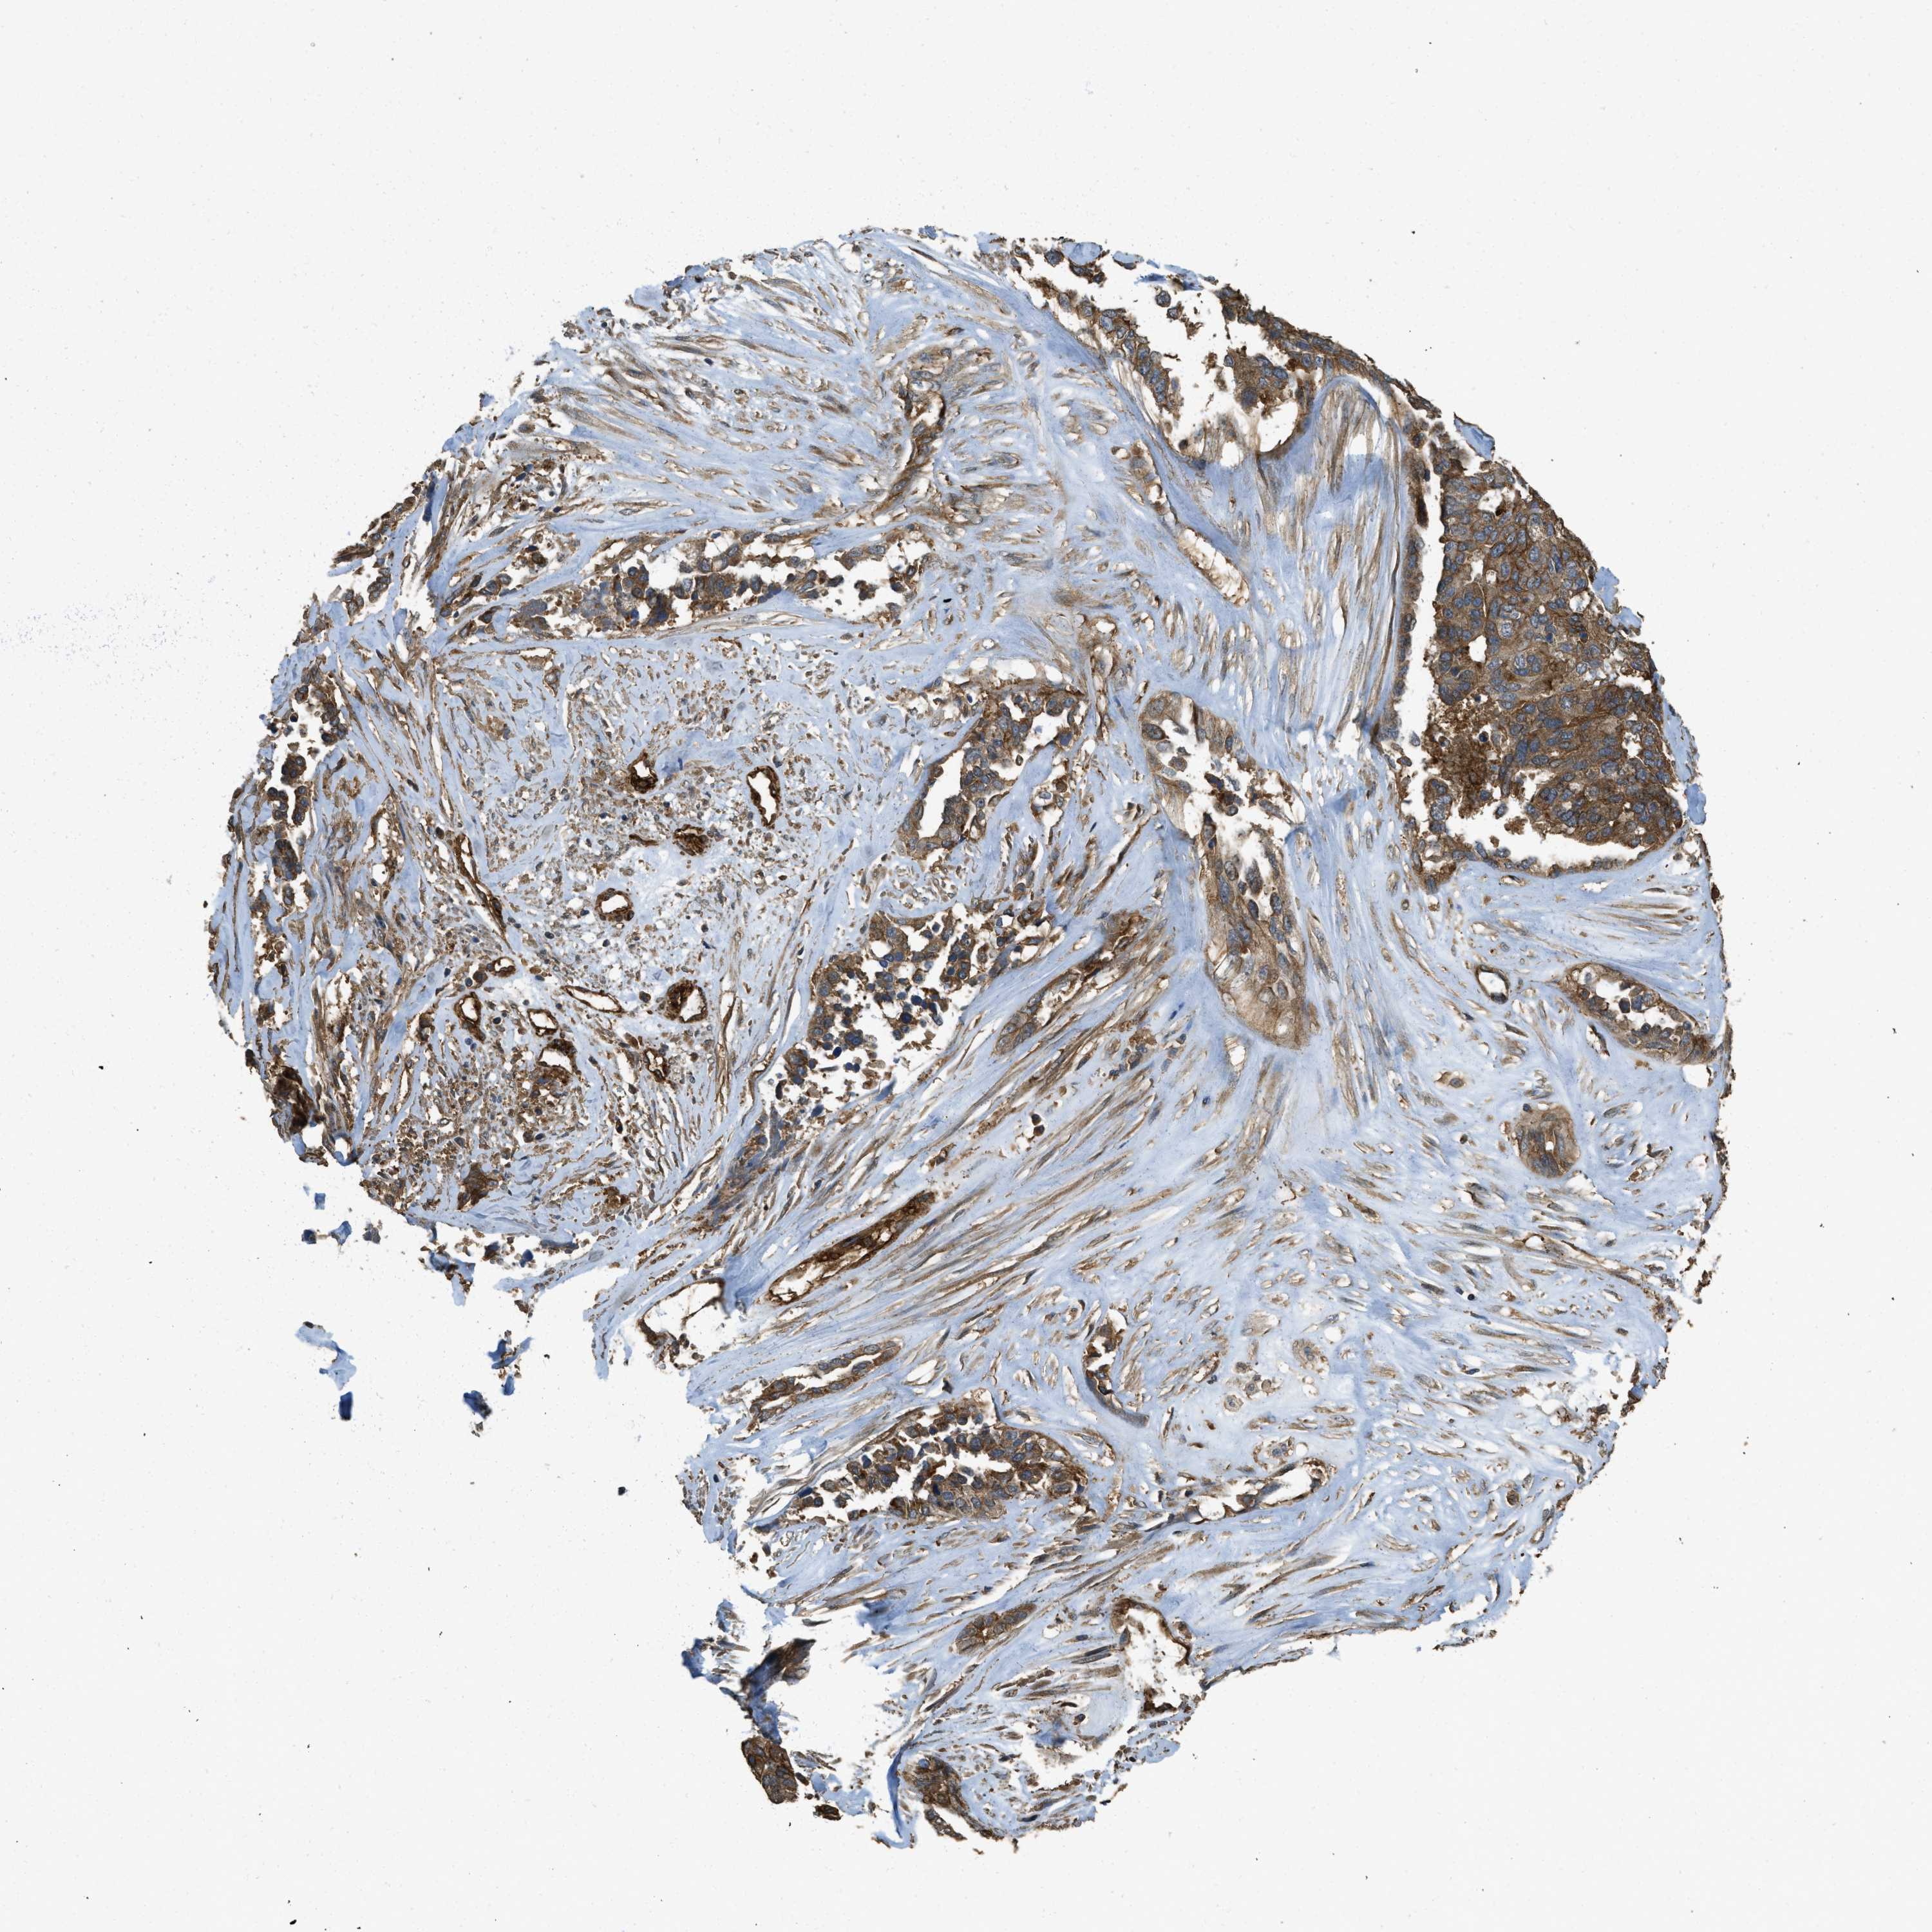

OVARIAN CANCER - Protein expressioni

A mouse-over function shows sample information and annotation data. Click on an image to view it in a full screen mode. Samples can be filtered based on level of antibody staining by selecting one or several of the following categories: high, medium, low and not detected. The assay and annotation is described here.

Note that samples used for immunohistochemistry by the Human Protein Atlas do not correspond to samples in the TCGA dataset.

Antibody stainingi

Antibody staining in the annotated cell types in the current human tissue is reported as not detected, low, medium, or high, based on conventional immunohistochemistry profiling in selected tissues. This score is based on the combination of the staining intensity and fraction of stained cells.

Each image is clickable and will lead to virtual microscopy that enables deeper exploration of all samples and also displays staining intensity scores, fraction scores and subcellular localization as well as patient and tissue information for each sample.

Antibody HPA009285

Antibody HPA017139

Antibody CAB017826

Cystadenocarcinoma, serous, NOS

Carcinoma, endometroid

Cystadenocarcinoma, mucinous, NOS

Carcinoma, NOS